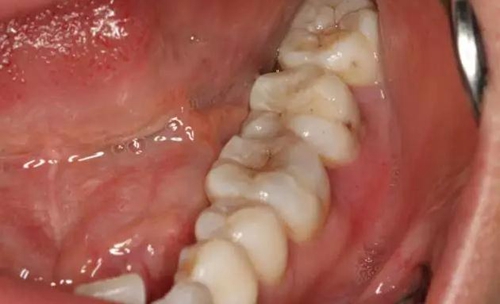

圖1.患者自述右側下后牙牙齦紅腫,咀嚼不適。術前口內(nèi)像:37頰側牙齦紅腫

10.jpg